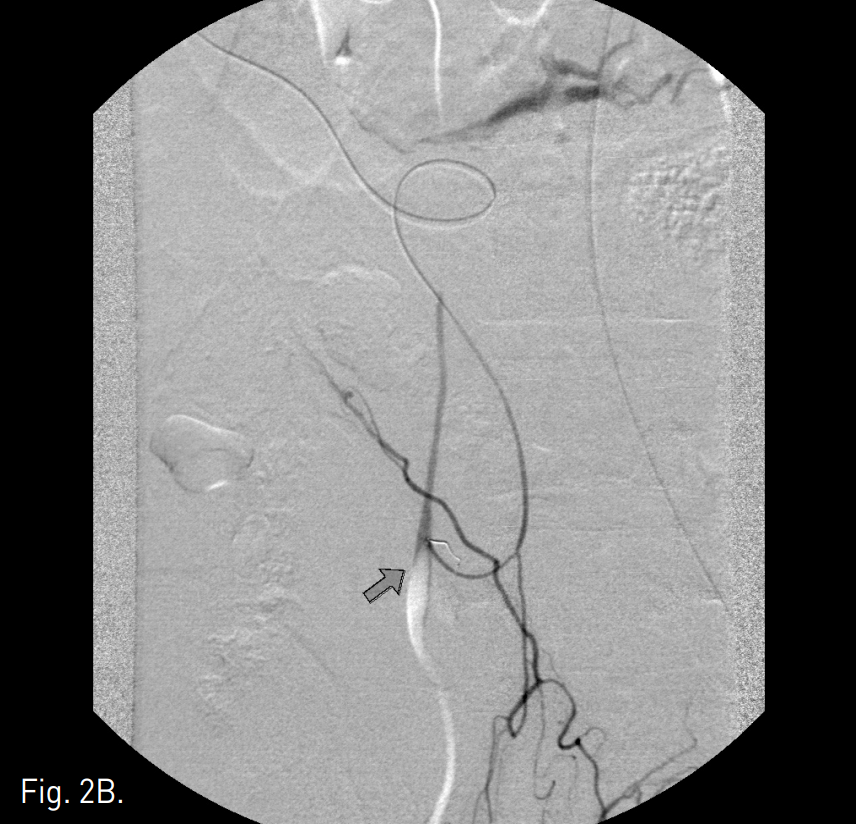

Fig. 1

A, B. Celiac angiogram of delayed phase (A) and selective angiogram of the right gastroepiploic artery (B) show extravasation of contrast media (arrow) from an omental branch of right gastroepiploic artery.